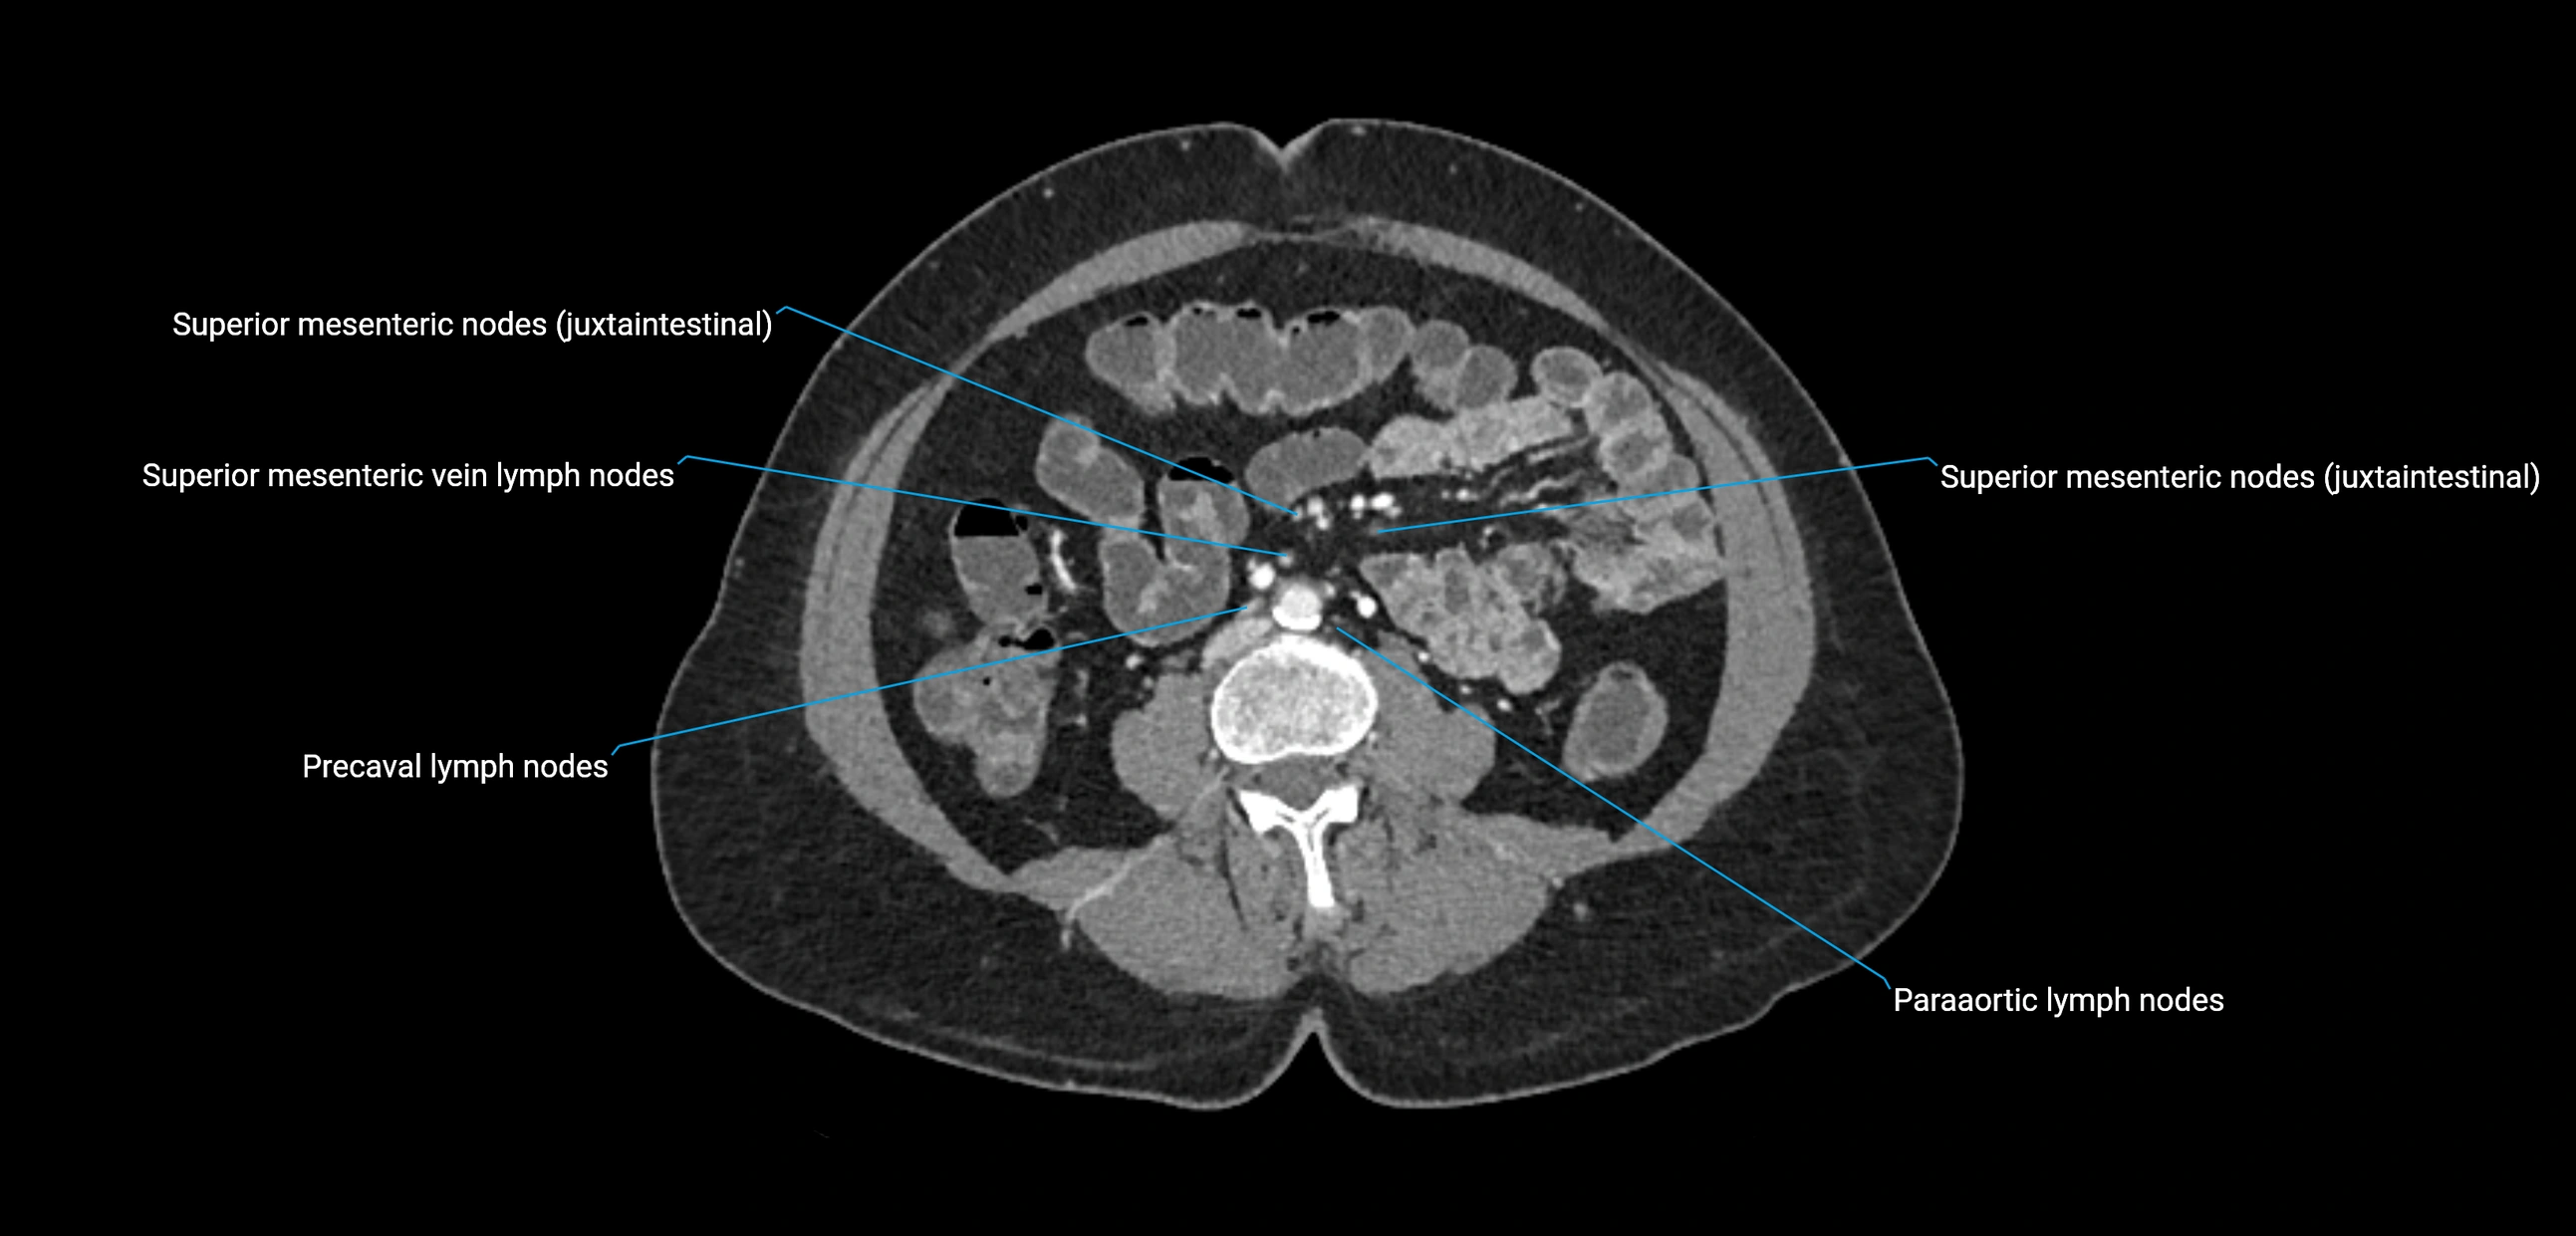

The lateral aortic lymph nodes (also called para-aortic lymph nodes) are a major group of retroperitoneal lymph nodes located along the abdominal aorta and its branches. They lie between the diaphragmatic crura superiorly and the bifurcation of the aorta at L4 inferiorly.

They are positioned on both sides of the abdominal aorta:

• Right lateral aortic nodes: adjacent to the inferior vena cava (IVC)

• Left lateral aortic nodes: lateral to the abdominal aorta

These nodes receive lymph from a wide range of abdominal and pelvic structures. Specifically, they drain lymph from the kidneys, suprarenal glands, gonads (testes/ovaries), uterus, uterine tubes, and pelvic organs, before converging into the lumbar lymphatic trunks, which terminate in the cisterna chyli → thoracic duct.

• Nodes appear as soft-tissue density nodules adjacent to the aorta and IVC

• Calcification may be seen in chronic infections (e.g., tuberculosis)

CT Post-Contrast:

• Normal nodes enhance homogeneously

• Malignant nodes may show heterogeneous enhancement, central necrosis, or conglomerate formation

• Size >1 cm short axis is suspicious, though morphology and distribution are equally important

CT image

image